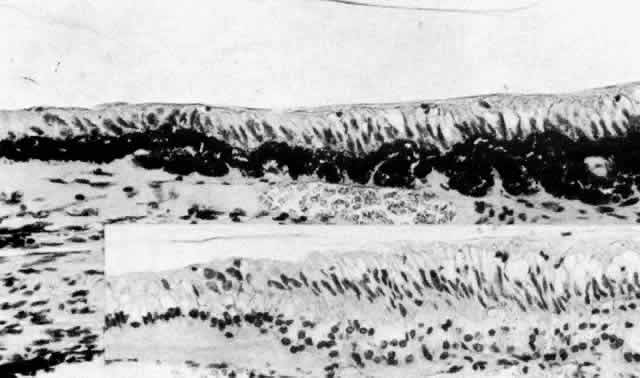

The NPE of the ciliary body stretches in a continuous layer from the root

of the iris to the ora serrata. As the transition from pigmented iris

epithelium occurs, melanin granules in the inner layer suddenly decrease

in number, and the cells become slightly smaller (Fig. 12). In the pars plicata the NPE cells are cuboidal, 12 to 15 μm in width, with

central nuclei (Figs. 13A and 13B). The knobbiness that develops during aging is due to small nodular proliferations

of NPE cells, especially on the minor plicae (Fig. 13C). In the young eye the cells of the pars plana are also cuboidal, but

with growth they become thinner and more columnar, sometimes reaching

up to 30 μm in height and 5 to 10 μm in width (Fig. 13D). In the posterior half of the pars plana, some NPE cells tilt forward

as though responding to anterior zonular traction, while others may be

inclined posteriorly, suggesting complex vectors of force in this region. The

nuclei are vertically oval and lie near the apex of the cells. The

epithelium here becomes very irregular with aging, showing hyperplastic

toothlike cell processes intertwining and extending up into the

vitreous and among the zonular fibers. At the ora serrata the ciliary

NPE joins the retina abruptly, highlighting the difference in thickness

of these two layers (Fig. 14).  Fig. 12. Frontal view of a ciliary process at its junction with iris, showing conversion

Fig. 14. Ora serrata in young adult, showing abrupt junction of ciliary nonpigmented

epithelium and sensory retina. A few hyalocytes are present in the

adjacent vitreous, and a degenerative cyst (C) is present in the peripheral

retina. (Toluidine blue, X 200) Fig. 14. Ora serrata in young adult, showing abrupt junction of ciliary nonpigmented

epithelium and sensory retina. A few hyalocytes are present in the

adjacent vitreous, and a degenerative cyst (C) is present in the peripheral

retina. (Toluidine blue, X 200)